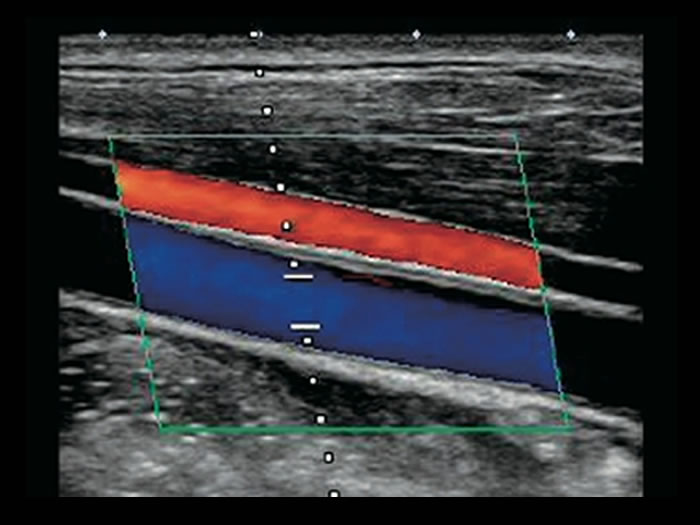

頸部(首)の超音波検査

脳疾患と生活習慣の関わりは非常に深く、特に三大生活習慣病の「高血圧症」「糖尿病」「高脂血症」については脳卒中に深く関わりがあります。

首の血管状態=全身の血管状態であるため、頸部(首)の超音波検査により脳梗塞につながる動脈硬化の進行具合を推測できます。

生活習慣病の早期診断に大変有益な検査です。

症状が無ければ、脳ドック特設サイト(自費)で「頸動脈超音波検査付きコース」をご用意しています。